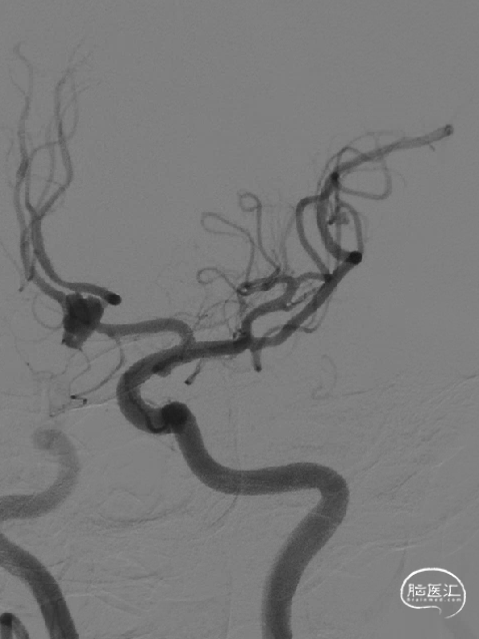

术前影像

术前DSA影像